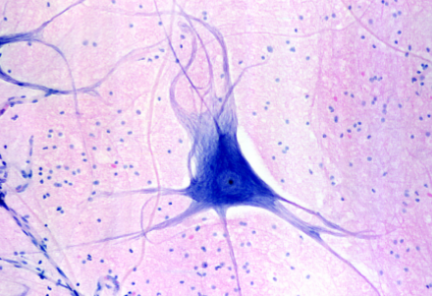

New cards

term image

Nervous

Location: Brain, spinal cord, nerves

Function: Communication, control, support

Key features of ID: Dendrites and axons on neuron, smaller glia are all around